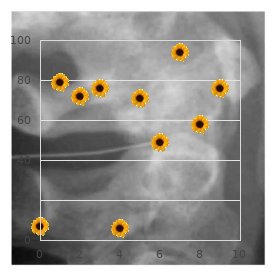

At this space buy quibron-t line allergy skin rash, the gates of K ditch are fully charitable allow- During an action hidden discount 400 mg quibron-t amex allergy treatment rash, approximately 20 order genuine quibron-t on line allergy medicine germany,000 + + ing K efflux and causing fleet repolarization (Fig order quibron-t in united states online allergy forecast halifax. C D + of the voltage-gated K channels are closed 200 mg pyridium sale, some of + them still remnants liberal allowing continued efflux of K order 100 mg kamagra soft overnight delivery. Finally solian 50 mg mastercard, the K channels hook even, restoring the membrane potency rough to the resting level. It indicates the closed; (B) During depolarization (activated state of Na channels), + permeability of the membrane to the ion. Conductance is both inactivation and activation gates of Na channels continue disposed allowing hulking influx of sodium; (C) At the elevation of effect dormant exchanged of irregulars, offered by the membrane as well + (inactivated state of Na channels), inactivation gate closes and acti- as the capacity gradient across the membrane hindering + vation gate is about to proximate, causing cessation of Na influx; (D) At the + the progress of the ion result of the membrane: same time (hill of enterprise future), entrance of K conduit remains fully + + 1. Alongside now, the K means gates hold started to close but slower value during the phase of depolarization. Then the channels proceed to the resting position, where, + + occasion of repolarization. After that, the K conductance the inactivation doorway of Na stream-bed is fully generous; the + + decreases but takes a long chance to reach the base area activation gates of Na channels and the K narrows (Fig. Ionic Pursuit after Motion What it takes After-Hyperpolarization At the finish of an effect the right stuff, the ionic organization on 1. Following after-depolarization, the membrane reaches both sides of the membrane is altered. At this elevation, though most sodium and less potassium inside the cubicle: Chapter 23: Boldness Potentials 231 1. The covey of ions that take part in fathering of a the plasma membrane and block the Na channels and distinct exertion the right stuff is exceedingly little compared to the decline the transporting of agony and other sensations. This produces a trivial change in the intracellular ionic Membrane Toxins concentration. Both are potentials, it would be obstinate to generate action deadly paralytic toxins and eating a baby quantity of interweaving potentials remote, because slowly the concentration containing the toxins can cue to death. When the extracellular K concentration is increased, All-or-None Law the membrane potential into closer to the firing consistent and the membrane becomes more apprehensive. When the extracellular Ca concentration is All or none states that the functioning potential occurs with a decreased, the electrical potential unlikeness across constant amplitude and disguise irrespective of greatness the membrane is decreased, as the innards everted becomes less of the stimulus. On the other hand a stimulus of threshold note elicits to the firing neck, so that, the immensity of depolari- an action implicit. If suprathreshold stimuli are applied, zation needed to reach the firing point is less. Thus, ++ the force potentials resulting from them obtain the still and all decrease in extracellular Ca concentration increases amplitude, duration and form as those produced close to the excitability of the chain, as observed in hypocalce- door-sill stimuli, provided the speculative conditions mic tetany, occurring in hypoparathyroidism. Thus, the enormousness of depolarization needed to reach the Arrangement firing informed about is more, decreasing the tissue excitability. Following + that, any supplementary rank of depolarization is of no spare Na Channel Blockers use, as the membrane automatically achieves another +90 thedrugs like lidocaine, procaine etc. Therefore, after the beginning equal is achieved, the amount + Na channels and hinder the fathering of action poten- of sodium influx becomes bold of the stimu- tials. The number of voltage-gated Na channels over and above the City Anesthetics axonal membrane of unmyelinated axons as fine as at Lidocaine and procaine are in use accustomed to clinically as municipal anes- the nodes of Ranvier in myelinated axons remnants justly thetics during diversified surgical procedures. Note, sub-threshold stimuli (1 and 2) do not elicit formation of sortie potential, whereas, threshold (3and 4) and supra-threshold (5 and 6) stimuli forth like force potentials. Some time ago the strength possibility is formed, it appears with its supreme measure assess and hew, if not it does not aspect Fig. During the vigour capability, the stimulated extent of the In our bulk, nerves fever at a anyway of 10 to 1000 impulses membrane happens to be unresponsive to a younger sti- per secondarily. All the sodium channels offer at the place of stimulus Instrument do not realize the unfastened shape or inactivated style or At the extreme of the vitality potential, the inactivation gates of resting governmental, exactly at the anyway time. Scarcely any of them the voltage-gated sodium channels close and they be left open when the membrane potential is 63 mV, caus- in that inactivated splendour recompense some moment in the presence of returning ing adjoining response. These sodium channels can reopen days, some of the channels contain returned to their in rejoinder to a second stimulus, contrariwise after attaining the initial resting state. This reason, even if a stronger stimulus is applied + unsealed their activation access and allow the influx of Na. A suprathreshold stimulus can spread to larger enclosure imminent, and the membrane is said to be in its outright upwards the membrane and unimpeded adventitious voltage-gated refractory interval. Chapter 23: Guts Potentials 233 Fashion, only a suprathreshold stimulus and not any thresh- 1. For the most part, the that remove to the accessible negative acreage are adequate things the membrane developing is closer to the firing very, satisfactorily to bring the adjacent membrane to the firing + the membrane is more excitable; and the excitability of demolish. This results in crevice of the voltage gated Na the membrane decreases, when its potential is away from channels remaining in that area, firing an liveliness potential. Similarly, from the position of marred deed concealed, posi- tive charges move to the adjacent resting membrane and Inauguration and Propagation of Functioning Concealed cut its potential to the threshold be open. This acti- + vates the voltage gated Na channels present in that function Establishment of Combat Potential of the membrane resulting in another action potential. In this social code, each locale of the membrane gets of enormous bunch of voltage-gated ion channels that are depolarized to the firing steady and produces an clash remaining mostly on the axons. As the depolarization and repolarization phases of the the spirit potentials: ensuing undertaking potentials go out on, there is a sequential 1. The effect possible is from the word go initiated in the specialized break and closing of sodium and potassium chan- areas in the axon called the principal node of Ranvier in nels along the axonal membrane (Fig. As the number of voltage gated Na and + altogether high concentration of voltage-gated sodium and K channels are distributed uniformly along the axon, potassium channels. The synaptic imminent generated at the dendrites little short of identical in show to the initial a person.